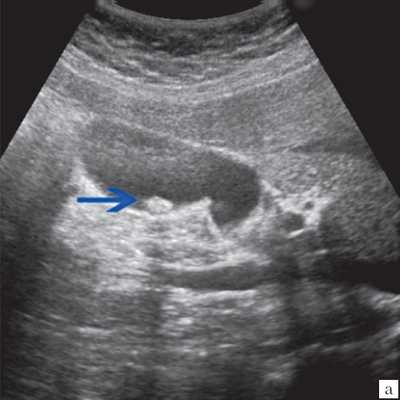

Клиническая картина желчнокаменной болезни многообразна [5-6, 10]. Условно выделяют хроническую болевую, хроническую рецидивирующую, диспептическую, стенокардитическую и ряд других клинических форм. Характерным ультразвуковым признаком конкремента в желчном пузыре является его акустическая тень. Такая тень возникает из-за высокой плотности камня по сравнению с мягкими тканями. Наличие или отсутствие тени помогает отличить камень от полипа желчного пузыря (рис. 4).

а) Одиночный конкремент желчного пузыря (подвижная гиперэхогенная структура, дающая четкую теневую дорожку).